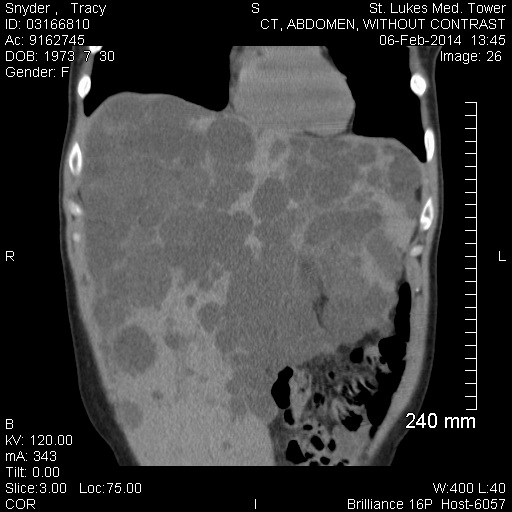

This disease is very rare, so rare that our transplant surgeon, who is top ranked and has done over 2.000 liver transplants, has done ten transplants on a polycystic livers. He was confident that the surgery would be a success, the point is that this is VERY RARE! After six hours of surgery, 4 hours just to get the sick one out, a collapsing lung, and several people to lift the polycycstic organ, it was a success. A healthy liver is the size of two fists and weighs 8-12lbs. The liver they removed was 43 pounds and had compressed every other organ in my body.